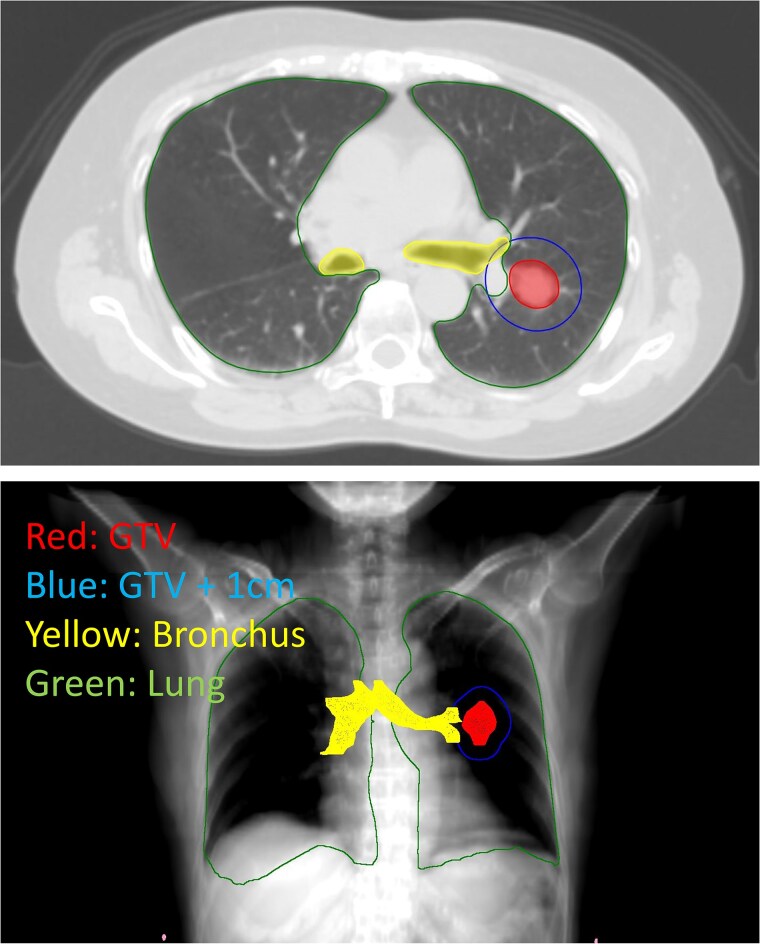

本研究探讨了立体定向体放疗(SBRT)治疗中枢性早期非小细胞肺癌(NSCLC)时症状性放射性肺炎(RP)的危险因素和支气管剂量限制。我们回顾了245例接受SBRT治疗的早期NSCLC患者,其中78例肿瘤位于主支气管或大支气管3cm内的患者被纳入本研究。采用α/β值为3的线性二次模型,将剂量-体积直方图数据转换为4个分数的当量。在调整临床因素后,为了检验剂量参数对≥2级RP的独立影响,采用以死亡为竞争风险的Fine-Gray模型进行评估。中位随访时间为44个月,≥2级和≥3级RP的4年累积发生率分别为22.5%和8.5%。调整临床因素后,6个支气管剂量学因素与≥2级RP显著相关。肺剂量学因素与≥2级RP无显著相关。在支气管的显著剂量学因素中,支气管V35Gy的危险比最高(HR 1.24, 95% CI 1.03 ~ 1.49, P = 0.027)。基于受试者工作特征曲线分析的支气管V35Gy最佳阈值为0.04 cc, V35Gy≤0.04 cc组与bb0 0.04 cc组4年≥2级RP发生率分别为15.7%和37.0% (P = 0.036)。在中枢性早期NSCLC的SBRT中,支气管V35Gy

The present study investigated risk factors and bronchial dose constraints for symptomatic radiation pneumonitis (RP) in stereotactic body radiotherapy (SBRT) for central early-stage non-small cell lung cancer (NSCLC). We reviewed 245 patients with early-stage NSCLC treated with SBRT, and 78 patients with a tumor within 3 cm of the main or lobar bronchus were included in this study. Dose-volume histogram data were converted to a 4-fraction equivalent using the linear-quadratic model with an α/β value of 3. To examine the independent effects of dose parameters on grade ≥ 2 RP after adjusting for clinical factors, the Fine-Gray model with death as a competing risk was used for evaluation. With a median follow-up period of 44 months, the 4-year cumulative incidence of grade ≥ 2 and ≥ 3 RP was 22.5% and 8.5%, respectively. After adjustment for clinical factors, 6 bronchial dosimetric factors were significantly associated with grade ≥ 2 RP. Lung dosimetric factors were not significantly associated with grade ≥ 2 RP. Among significant dosimetric factors of the bronchus, bronchus V35Gy had the highest hazard ratio (HR) (HR 1.24, 95% CI 1.03-1.49, P = 0.027). The optimal threshold for bronchus V35Gy based on receiver operating characteristic curve analysis was 0.04 cc. The 4-year incidence of grade ≥ 2 RP in the bronchus V35Gy ≤ 0.04 cc vs. >0.04 cc groups was 15.7% vs. 37.0% (P = 0.036). In SBRT for central early-stage NSCLC, bronchus V35Gy < 0.04 cc is the definitive indicator for preventing grade ≥ 2 RP.